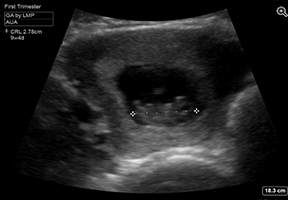

Pelvic Transabdominal (TA) Intrauterine Pregnancy (IUP) Crown Rump Length (CRL) Image